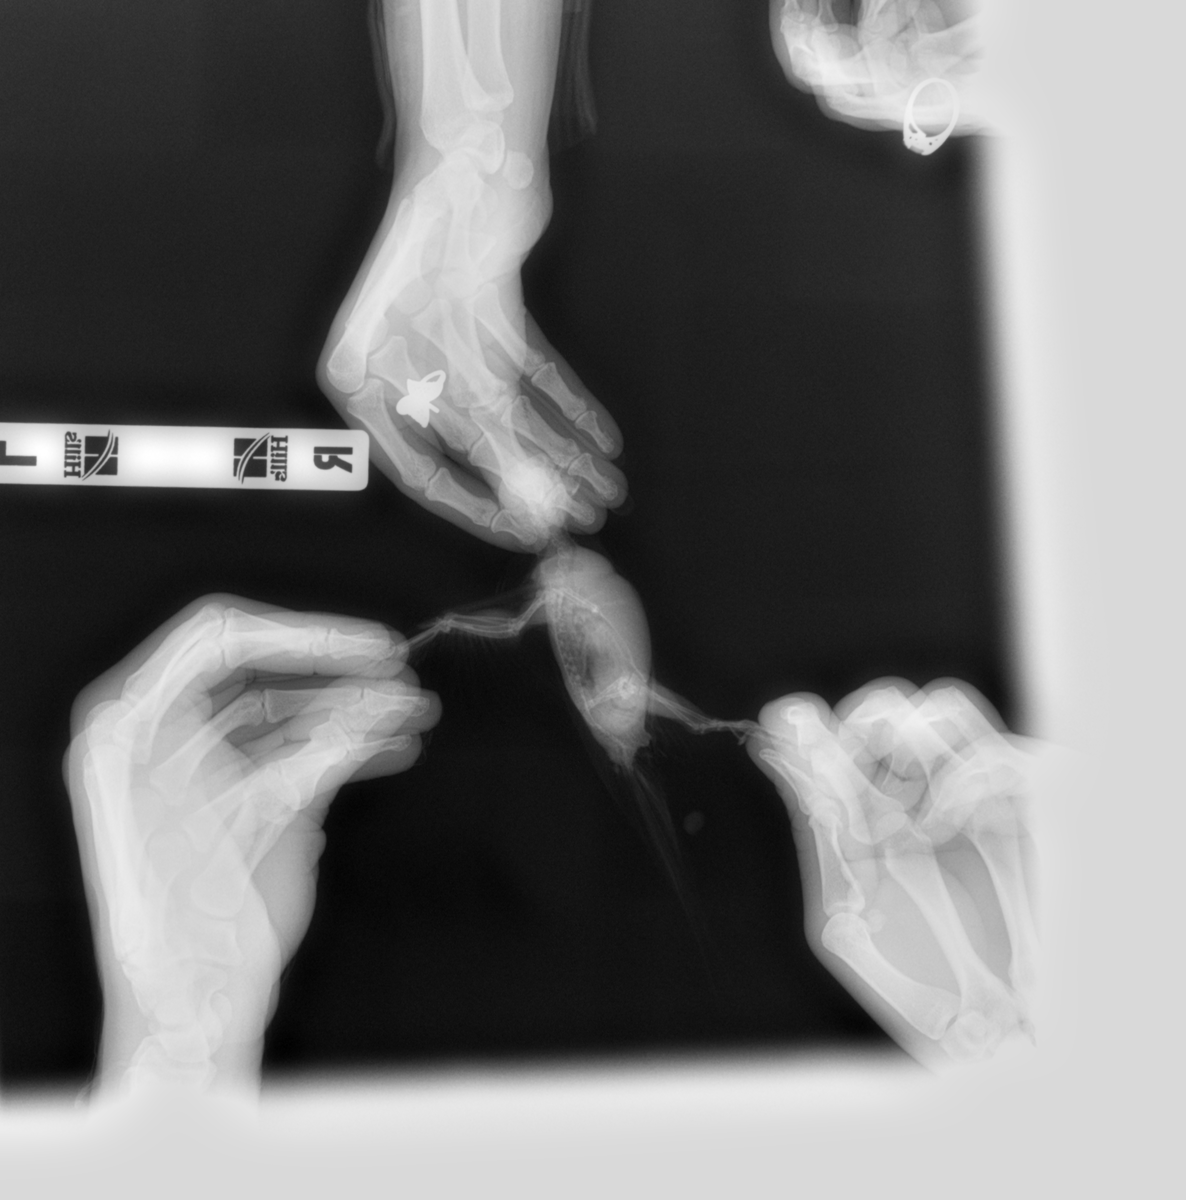

Venni Опубликовано 24 марта, 2019 Автор #117 Опубликовано 24 марта, 2019 (изменено) Всем здравствуйте. Сегодня были в вет.клиники. Врач брал мазок из зоба и клоаки- есть большое количество тонких, длинных палочек, но не мегабактерий, я ему даже фото с инете показывала мегабактерий под микроскопом, сказал не они, может и есть мегабактерии, но на фоне приёма противонрибковых лекарств, он их не видит, так же сделали рентген, рентген показал, что кишечник увеличен, печень в норме, полное описание скинет мне на почту вечером. По поводу бак.басева, у них только можно сделать на сальмонеллу, криптоспоридии и туберкулез, но этого мало, говорит вам в Воронеже нигде полный бак.пасев не сделает, делают только надо в Москву ехать, там лаборатории делают. Завтра буду звонить в обл.ветеринарную лабораторию, просить сделать бак.пасев., если нет, то хоть на эти 3 инфекции сдам, хотя толку мало. Как поддержать сейчас кишечник? Он ничего не назначил, говорит нужны анализы. Изменено 24 марта, 2019 пользователем Venni

KamaRo Опубликовано 24 марта, 2019 #118 Опубликовано 24 марта, 2019 @Venni выложите снимок рентгена, Зося его посмотрит и почитает. На счет мегабактерий и препаратов - болезнь неизлечимая, поэтому возбудитель может присутствовать в анализах. Как то удивительно, что обыватель ветеринару скидывает фото мегабактерий. Обычно вет.орнитологи, которые проводят и лабораторную диагностику, сами с атласами работают и консультируются у коллег более высокой квалификации. Нам вет.орнитолог даже группу возбудителей по микроскопии помета назвал, а посевом уже вид определяли и соответственно чувствительность к препарату. А как у собак/кошек возбудителей находят, ведь явно посевы делают? Областная вет.лаборатория как правило делает и бакпосев и микологический. На счет как поддержать кишечник, назначения уже дали - пробиотики, гепатопротекторы

KamaRo Опубликовано 24 марта, 2019 #120 Опубликовано 24 марта, 2019 (изменено) @Venni снимки выложить в тему, как фото выкладываете, так и их. раз мегабактерия под вопросом, то обязательно сделайте посев на грибы, уж он то не обманет. Изменено 24 марта, 2019 пользователем KamaRo

Venni Опубликовано 25 марта, 2019 Автор #124 Опубликовано 25 марта, 2019 (изменено) Помёт на самом деле жёлто-зелёный, сейчас смотрю на фото очень светлый, хотя в телефоне цвет жёлто-зелёный. Выкладываю рентген. 9999_00014674.DCM 9999_00014673.DCM Изменено 25 марта, 2019 пользователем Venni

Venni Опубликовано 25 марта, 2019 Автор #125 Опубликовано 25 марта, 2019 (изменено) Сегодня сдали комлексный бак.посев с чувствительностью к антибиотикам, бактериофагам и антимикотическим препаратам. Пришлось вчера звонить в Москву в веттест, объяснила какой анализ мне нужен, сказали сделают, дали перечень вет.клиник в Воронеже с которыми они работают, где возьмут посев, правда долго делать будут 9-21 день, взависимости от роста. Изменено 25 марта, 2019 пользователем Venni

Venni Опубликовано 26 марта, 2019 Автор #127 Опубликовано 26 марта, 2019 @KamaRo Здравствуйте. Я выложила выше рентген, только почему то не фото, а файлами у меня получилось. Хотела узнать, можно ли птице давать какие- нибудь спазмолитики, мне кажется у неё болит живот, сегодня активность спала и когда она сидит на жёрдочке, то не прямо, а с наклоном вниз, где то читала, что это у птицы живот болит.

Venni Опубликовано 27 марта, 2019 Автор #134 Опубликовано 27 марта, 2019 @Zosia @Zosia Здравствуйте. Посмотрите пожалуйста наш рентген. На сколько пострадали органы от мегабактерий. 9999_00014673.DCM 9999_00014674.DCM

Venni Опубликовано 28 марта, 2019 Автор #135 Опубликовано 28 марта, 2019 @Zosia Добрый день. Посмотрите пожалуйста наш рентген. Файлы еле открыла. Извините, не разбираюсь в технике совсем.